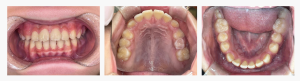

初診時の状態

・上の前歯が前方に突出している

・前歯の並びにガタつきがみられる

・このまま成長すると叢生が強くなる可能性

成長期に入り始めたタイミングで、歯並びが乱れやすい状態でした。

◆ 診断名・初診時の状態

診断名:上顎前突(じょうがくぜんとつ)、叢生(そうせい)

初診時の診察では、

・上顎前歯の前方傾斜

・将来的にガタガタが進行する可能性

などの所見があり、

見た目の問題だけでなく、成長方向を整える必要があるケースでした。

▼ Before(治療前)